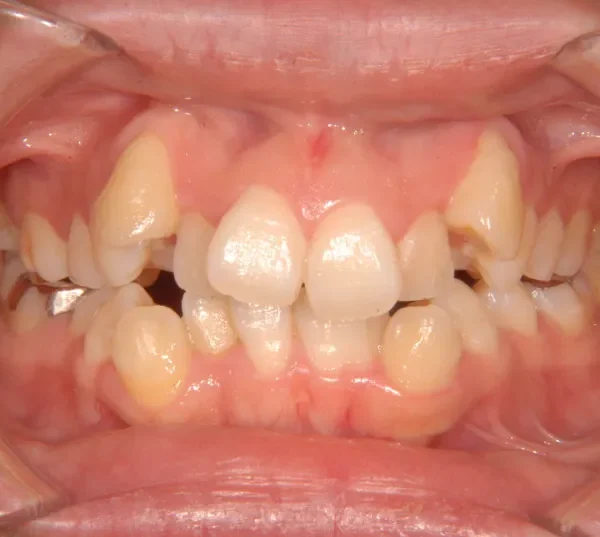

初診時年齢 19~29歳 (女性) 主訴 八重歯・ガタガタ・癒合歯

診断名 叢生 装置名

状態 ガタガタ・でこぼこに生えている(叢生)

八重歯(叢生)

八重歯で笑うと尖った歯が目立ちます。

上下ガタガタで、下の歯は癒合歯(2本がくっついて1本の歯)です。

初診